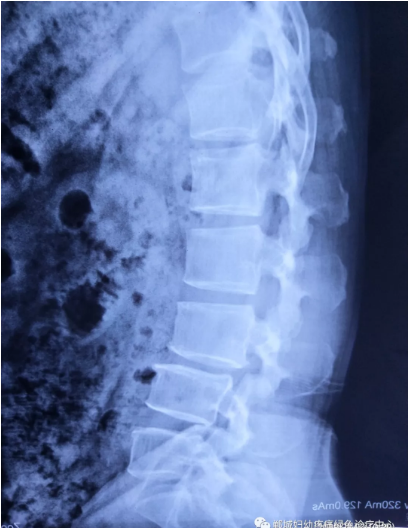

不經(jīng)意間聽到有人說醫(yī)院疼痛科可以不吃藥不打針,用無痛苦、無創(chuàng)傷的方法治療腰痛。陳女士就抱著試試看的心理來到了鄲城縣婦幼保健院疼痛科,疼痛科時(shí)慶祥主任詳細(xì)了解病情,結(jié)合腰椎磁共振及體征后告訴陳女士她不用手術(shù),通過腰椎脊柱定位周期減壓牽引系統(tǒng)(外星艙)也能解決腰痛、腰椎滑脫、腰椎反弓這些問題。陳女士未曾想到經(jīng)過十五天的治療后腰部及下肢放射性疼痛癥狀基本消失。陳女士感到十分激動與感謝,就在當(dāng)?shù)匦l(wèi)生院做了一個(gè)腰椎正側(cè)位x片和之前的片子作對比,發(fā)現(xiàn)腰椎滑脫明顯改善。她說道:感謝鄲城縣婦幼保健院疼痛科的所有醫(yī)護(hù)人員、感謝外星艙脊柱減壓治好了我的腰痛,也感謝告訴我來這里的人,她的一句話,讓我省了好幾萬元的手術(shù)費(fèi)!

治療后